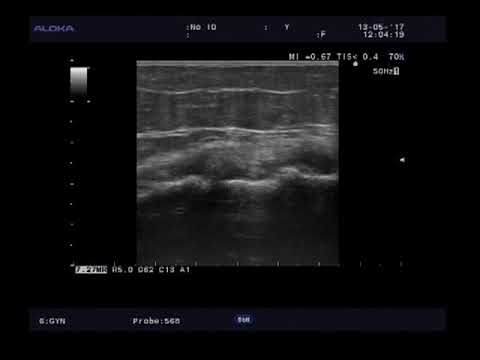

Рис. 12: Артроскопический снимок: Повреждение хряща в голеностопном суставе